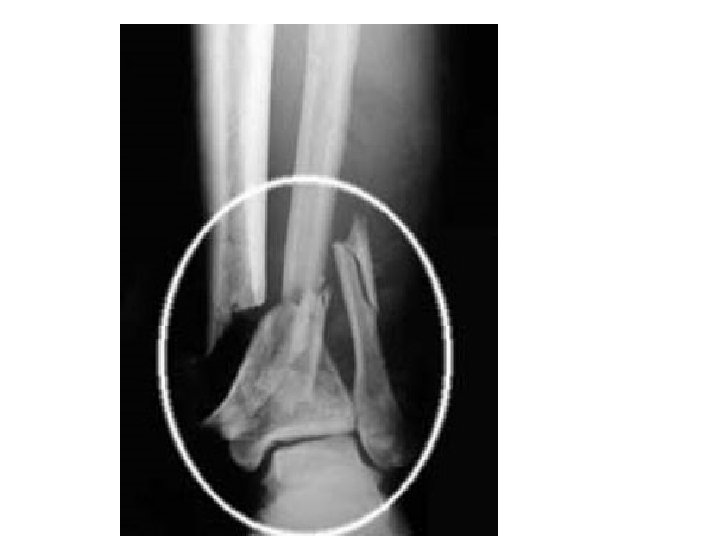

B. Fractures 1. Simple bone breaks cleanly, does not break through skin

B. Fractures 2. Compound broken ends protrude through the skin, risk of bone infection

B. Fractures 3. Greenstick Does not break completely Greenstick: (children)